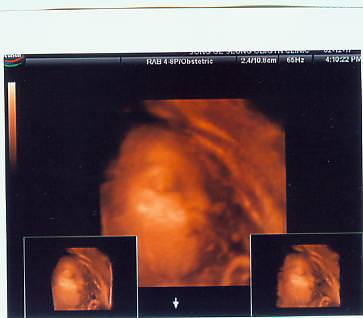

정말 웃기게 생겼죠?